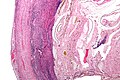

Pathology diagnosis of appendicitis can be made by detecting a neutrophilic infiltrate of the muscularis propria.

Periappendicitis, inflammation of tissues around the appendix, is often found in conjunction with other abdominal pathology.[60]

Micrograph of appendicitis and periappendicitis. H&E stain.

Micrograph of appendicitis showing neutrophils in the muscularis propria. H&E stain.